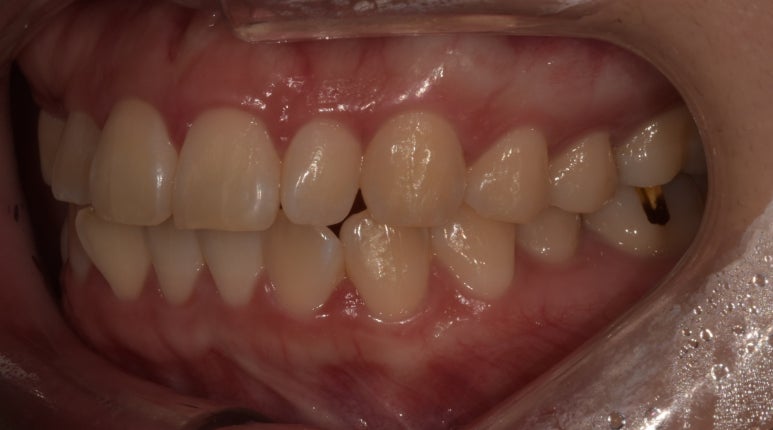

치료 전 사진

2023-03-02

처음 내원하셨을 때 환자분의 치아 사진입니다.

#13 치아가 결손된 상태였고, #22 치아는 다른 치아에 비해 크기가 작은 왜소치였습니다.

치료 전 오른쪽 치아 사진

우선은 오른쪽 10번대 치아는 #12~14를 브릿지로 연결해 #13 치아를 만들어주기로 했습니다.

치아 하나만 결손되었으니 임플란트로 치료할 수는 없는지 궁금하실텐데요.

임플란트도 가능은 하지만 현재 빈 공간이 좁은 만큼 크라운의 사이즈 역시 작아질 수밖에 없고,

뼈 구조물로 인해 뻐드러지거나 튀어나와보일 수 있는 점을 고려해 브릿지로 치료하기로 했습니다.

치료 전 왼쪽 치아 사진

20번대 치아는 #22가 왜소치인 점을 고려해 라미네이트로 치아 사이즈를 키우기로 했고,

#23 치아는 브릿지로 만들어질 #13 치아와 대칭을 맞추기 위해 치아를 약간 다듬어 라미네이트로 치료하기로 했습니다.